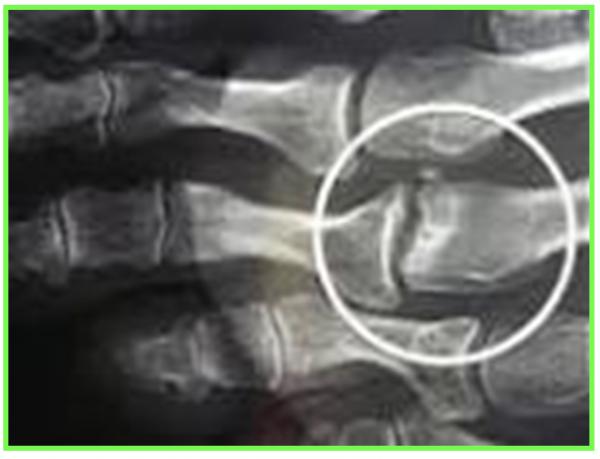

SYNDROME DU 2 EME RAYON :

Le Syndrome du 2ème rayon est un syndrome douloureux dû à une surcharge mécanique sur l’articulation métatarso-phalangienne du 2éme orteil.

L’évolution se fera par la suite vers une déformation progressive du 2éme orteil

En fonction de l’importance de la lésion de la plaque plantaire (fissure simple ou complexe, déchirure), cela crée une déviation de l’orteil, perte d’appui, chevauchement d’orteils, apparition d’une « griffe », dislocation articulaire métatarso-phalangienne.

RADIOGRAPHIE DU PIED EN CHARGE F + P, ECHOGRAPHIE

IRM : Bursite , rupture de la plaque plantaire